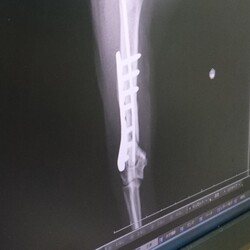

退院から1週間リハビリを耐えた雉白ちゃんの骨折はかなり良い状態に戻ってきました。

インプラントを右上腕骨に入れているため6月中は基本的にケージ内安静ですが、短時間ならジャンプをしないように目を離さず遊ばせてあげる許可が出たのでいっぱい遊んで血流を良くしたり刺激を与えてあげたいと思います。